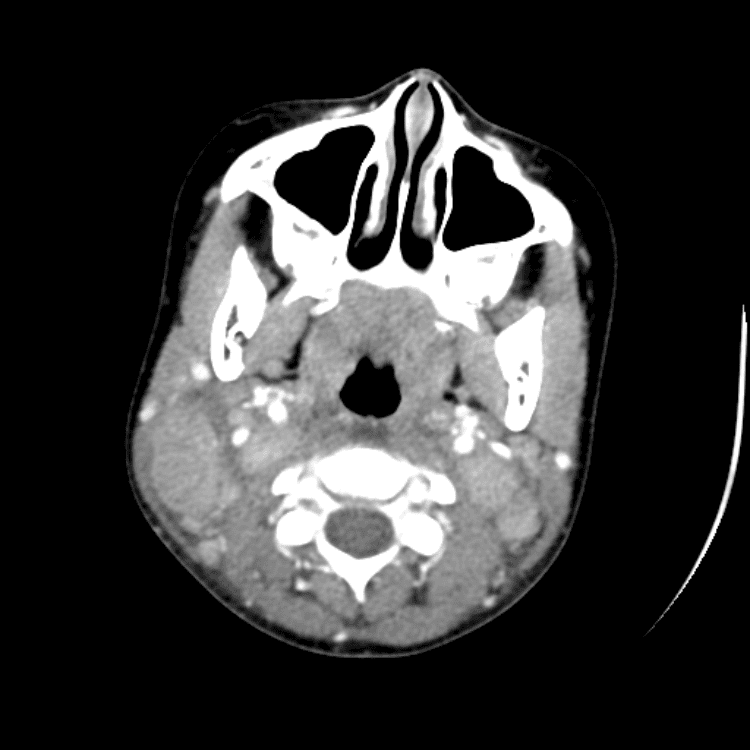

Head and Neck

Practice

Simulates call by including subtle or difficult cases and some normals.

27 cases